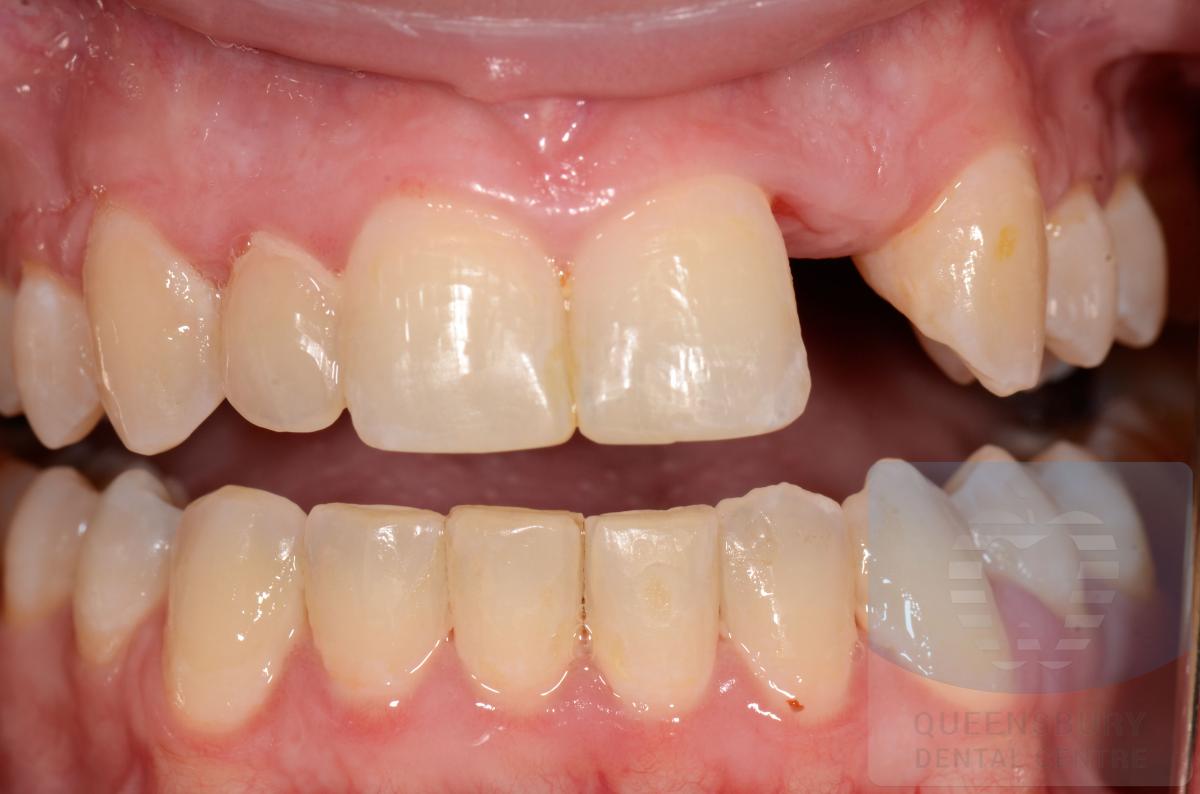

Missing teeth and loose dentures make many people avoid social settings because they are too self-conscious about their appearance. Current dental procedures, however, replace everything from a single missing tooth to a completely missing arch. Ask your dentist or dental specialist about the different dental options that are available to you. Don’t let another day go by without taking this important first step to restoring your confidence and your smile!